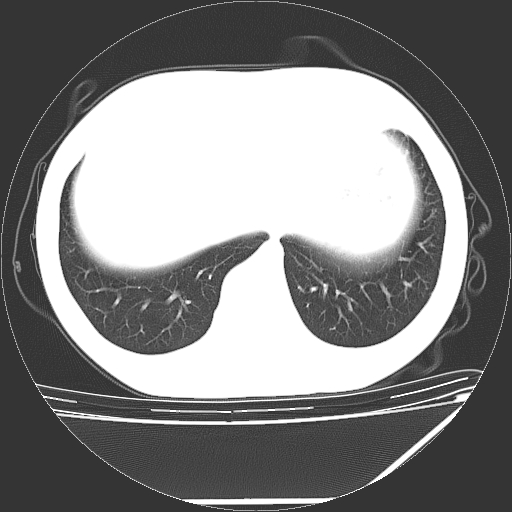

男,13岁,咳嗽、咳痰伴发热一周。

中上纵隔见多枚淋巴结肿大,部分相互融合成团片,左肺门增大,上叶支气管变窄,肺内多处斑片状 索条状及棉絮状致密影。临床“男,13岁,咳嗽、咳痰伴发热一周。”首先考虑:原发综合征!不除外淋巴瘤可能!

纵隔多发肿大淋巴结,部份有融合改变。双肺血管气管束增厚,以肺门为中心向外周散发,以左肺下叶为明显。考虑淋巴瘤可能性大。不除外原发综合征。

中上纵隔见多枚淋巴结肿大,部分相互融合成团片,左肺门增大,上叶支气管变窄,左肺支气管血管束增粗,可见磨玻璃样影。临床“男,13岁,咳嗽、咳痰伴发热一周。”首先考虑:淋巴瘤可能性大!

左肺野见淡片状影,病因整体多考虑结核

单纯看片子感觉左侧肺通气不畅,而不像肺内病变引起的纵隔病变。而且纵隔及左肺门都有淋巴结增大。首先还是考虑一下结节病,不排除淋巴瘤!!!